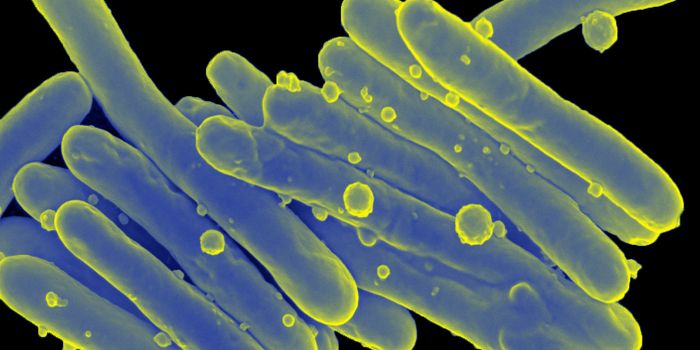

SEP 16, 2015MicrobiologyMethicillin-Resistant Staphylococcus Aureus (MRSA) is a dangerous bacterium that has become increasingly resistant to mu ...

NOV 30, 2016MicrobiologyLeprosy. We’ve all heard of it, but do you really know what causes it? What does the word make you think of ...

JUL 07, 2015Health & MedicineAntimicrobial resistance has been recognized as a significant global health priority that threatens to take modern medic ...

SEP 14, 2015MicrobiologyThis week Food Safety News named the 5 most dangerous foodborne pathogens. You may have heard of some of them due to med ...